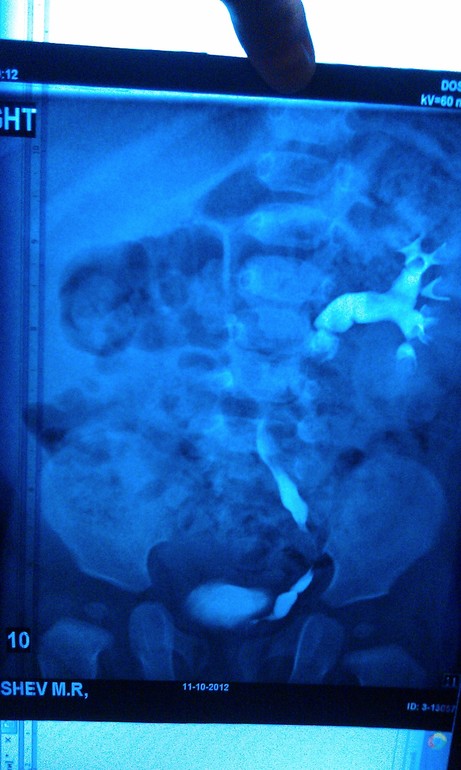

Урография

Максиим Викторович. Если возможно, могли бы вы прокомментировать нашу урограмму. Заключение рентгенологов и урологов разнятся. Хотелось бы послушать мнение третьего специалиста.

Олеся, я бы с радостью, но так снимки объективно оценить не смогу, тем более не зная клинической ситуации. Слева понятно, а с правой почкой что?